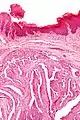

| Micrograph of a papillary hidradenoma with the characteristic papillary structures and epithelium with apocrine snouts. A fragmented overlying epidermis is seen at the top of the image. H&E stain. | |